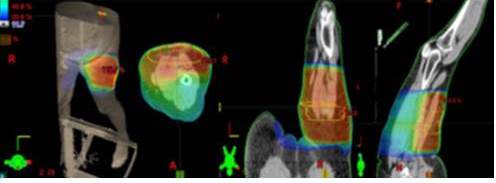

En relación al grupo de sarcomas de tronco y extremidades (60 pacientes), la edad promedio fue de 48,5 años, no hubo diferencia significativa en cuanto al sexo, fueron más frecuentes los liposarcomas (33,3 %) seguidos de los sarcomas pleomórficos (9,6 %), leiomiosarcomas y los sarcomas sinoviales (8,3 %). Según el estadio de la enfermedad, predominaron los estadios IIIA (26,6 %) y los II (23,3 %). En sólo 2 pacientes no se practicó cirugía y de los 58 restantes el 93,3 % fueron intervenidos quirúrgicamente una oportunidad, los otros 2 ameritaron más de 2 cirugías antes de la radioterapia. En el 68,3 % de las intervenciones se obtuvieron márgenes quirúrgicos negativos, en el 15 % márgenes negativos y 6,6 % tuvieron márgenes estrechos, en el resto de los casos estos no se especificaron. Sólo 8 pacientes recibieron tratamiento sistémico en sus distintas modalidades. La radioterapia se realizó de forma posoperatoria en casi todos los pacientes (57). La técnica de planificación más utilizada fue la conformada tridimensional (66,7 %) seguido de la convencional (21,7 %) y la dosis total promedio fue de 6 400 cGy (Cuadro 2 y Figura 3).

Las toxicidades más frecuentes durante el tratamiento radiante fueron la dermatitis grado II (53,3%) y dermatitis grado I (36,6%) (Cuadro 3). En cuanto a las toxicidades crónicas un paciente presentó neumonitis grado I, otra trombosis venosa profunda en el miembro inferior irradiado y 1 paciente desarrolló osteomielitis de fémur derecho, sin embargo, éstos dos últimos fallecieron por enfermedad a distancia, logrando en ellos control local de la enfermedad.

La mayoría de los pacientes (76,6 %) se encuentran vivos sin enfermedad, un paciente falleció sin enfermedad y sólo 11 pacientes (18,3 %) murieron por enfermedad (Cuadro 5).

El tiempo promedio de seguimiento fue de 54,2 meses y la mediana fue de 30,4 meses.

La supervivencia libre de enfermedad fue de 75,20 % y la supervivencia global se reportó en 77,4 % ( 2).